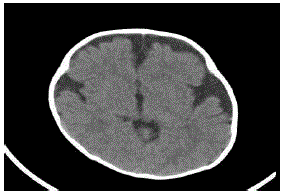

Lactente de sete meses de idade está em consulta de rotina de puericultura. A mãe teve uma gestação e parto sem intercorrências e nasceu com um perímetro cefálico de 35 cm. Ao exame neurológico, foi evidenciada uma fontanela ampla e depressível, perímetro cefálico de 48 cm, com marcos do desenvolvimento normais.

Na investigação, foi realizada tomografia computadorizada de crânio (ver abaixo).

enunciado 1663867-1

Qual é o diagnóstico?